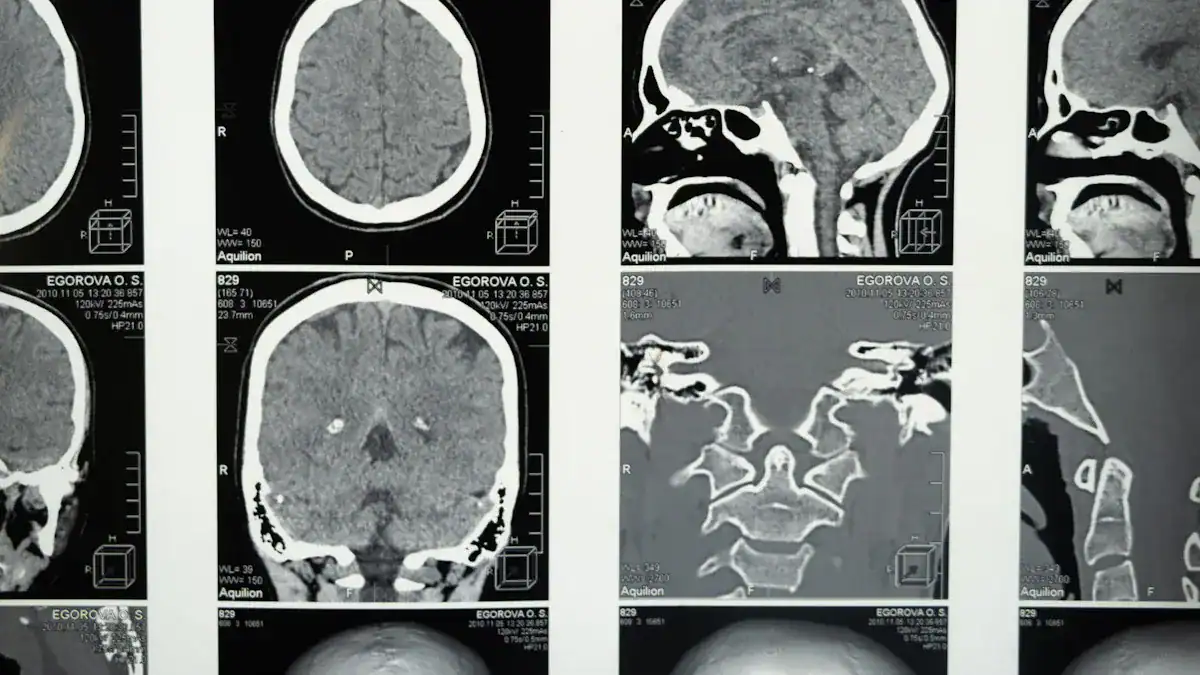

Imaging Tests: MRI and CT Scans

Imaging tests like MRI and CT scans are crucial for visualizing the brain and surrounding structures. MRI of the brain is a primary tool for assessing and differentiating suspected neurological conditions. These conditions include Alzheimer’s Disease and Vascular Dementia. MRI can help rule out neurodegenerative disorders.

It also screens for various chronic orofacial pain types. This excludes structural issues such as intracranial tumors, cysts, or trigeminal nerve vascular compression. A study of 125 patients showed intracranial pathologies in 48.8%. These included trigeminal neurovascular contact, cerebral small vessel disease, and space-occupying lesions. These scans help identify structural problems or signs of brain inflammation that could cause the burning sensation.